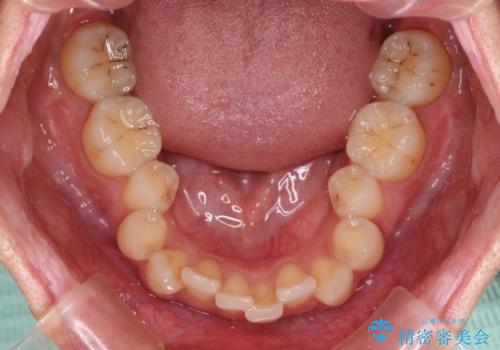

- 前歯のデコボコと強い咬みしめを気にして来院された患者様です。

インビザラインを用いて、前歯の叢生を解消するとともに、ディープバイトを改善していくこととしました。

海外へ転居する予定があったため、1日22時間以上の装着時間をしっかりと守っていただき、予定期間よりも早く、思っていた以上にきれいに仕上げることができました。